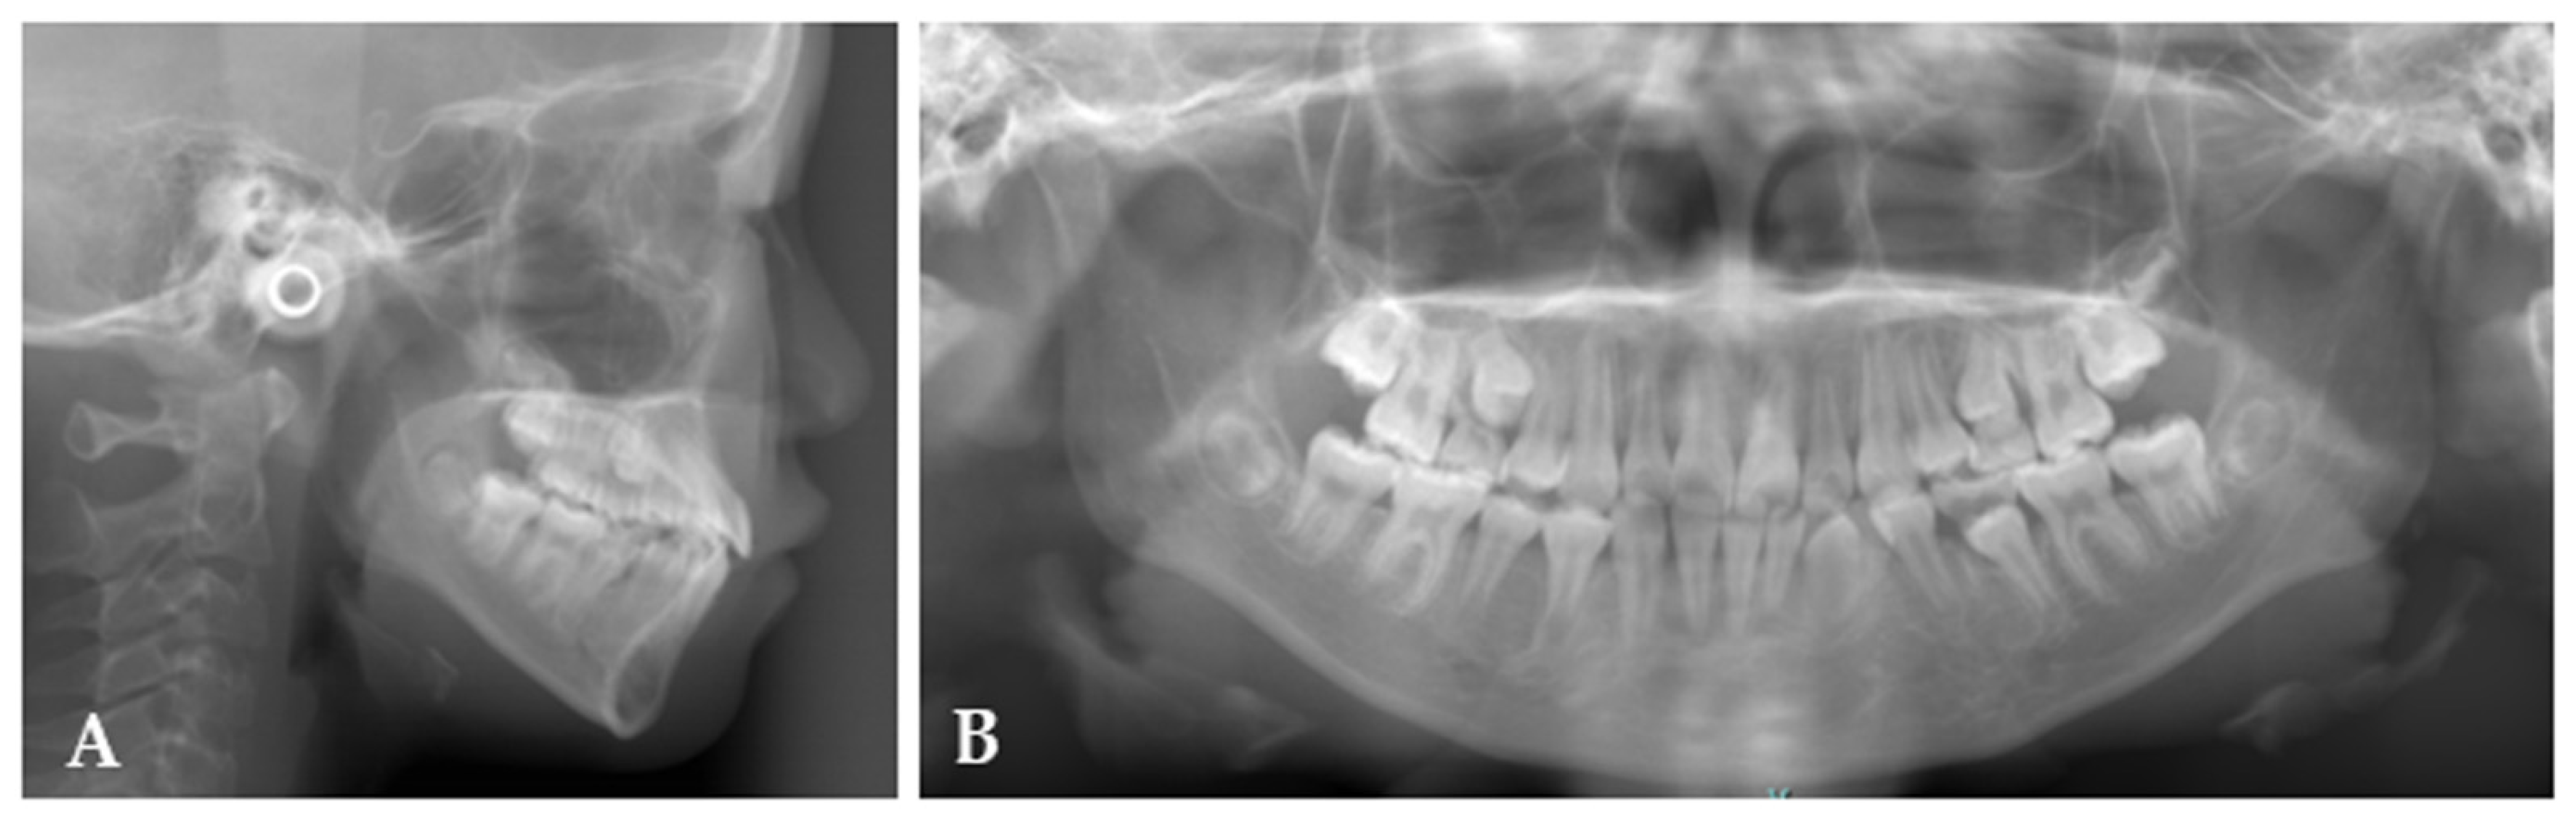

2. Case Report